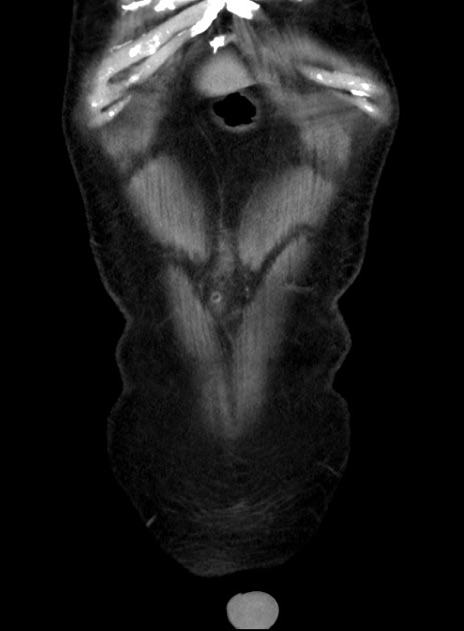

症例38(冠状断像)

【症例】70歳代 男性

【主訴】腹痛・嘔吐

【現病歴】昨晩より、嘔吐・腹痛あり。今朝になっても嘔吐あり。来院。

【既往歴】心臓バイパス手術、開腹胆摘、腸閉塞

【身体所見】BP 107/71mmHg、HR 116/min、腹部:平坦、軟、下腹部に軽度圧痛あり。反跳痛なし。

【データ】WBC 15100、CRP 0.32